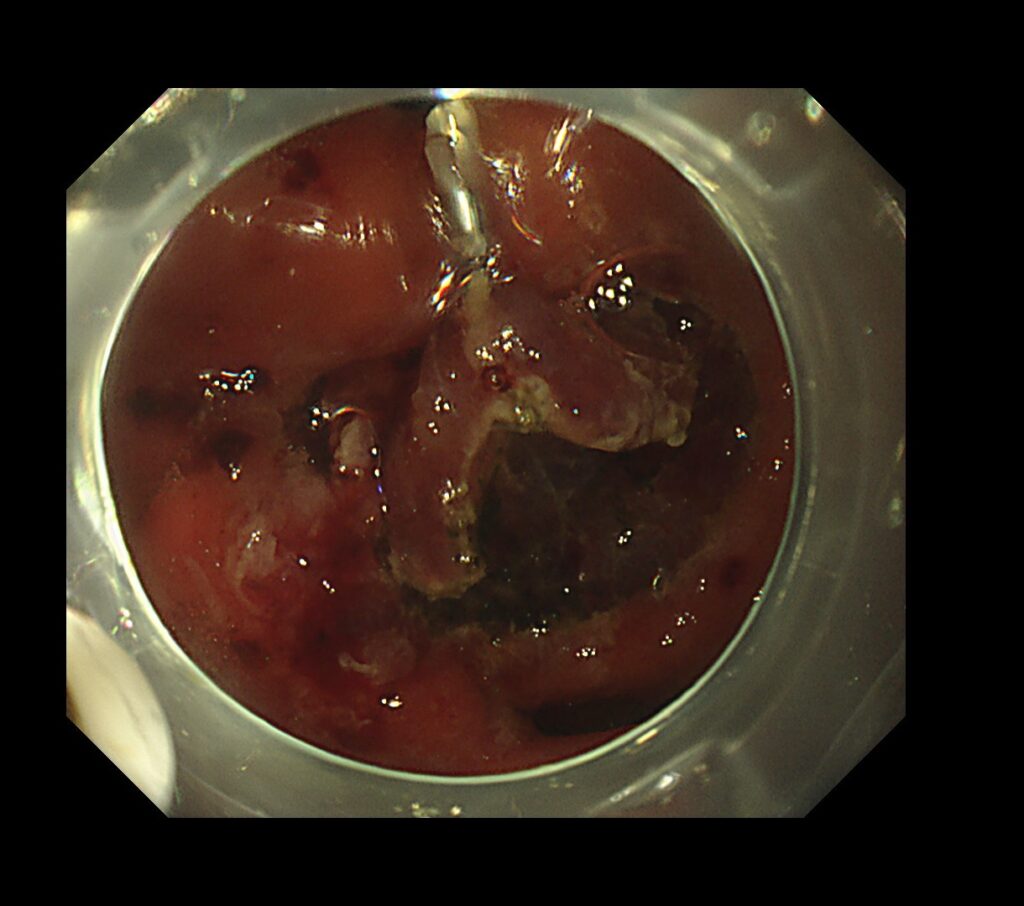

瘢痕近傍は全く視野確保がとれないため、独自で作った糸付きクリップで、病変を牽引し、切除ラインを視認しやすくします。

今回は、瘢痕上(過去に他院にESDを施行されている方)に発生したい癌のため、病変の直下は、繊維化と呼ばれる変化を起こしており、筋層と粘膜の間にスペースが無くなり、固くなる減少が起きます。

このような状況では、切除ラインが不明瞭となり、筋層切開➔胃壁穿孔を起こしうる病態が予想されます。